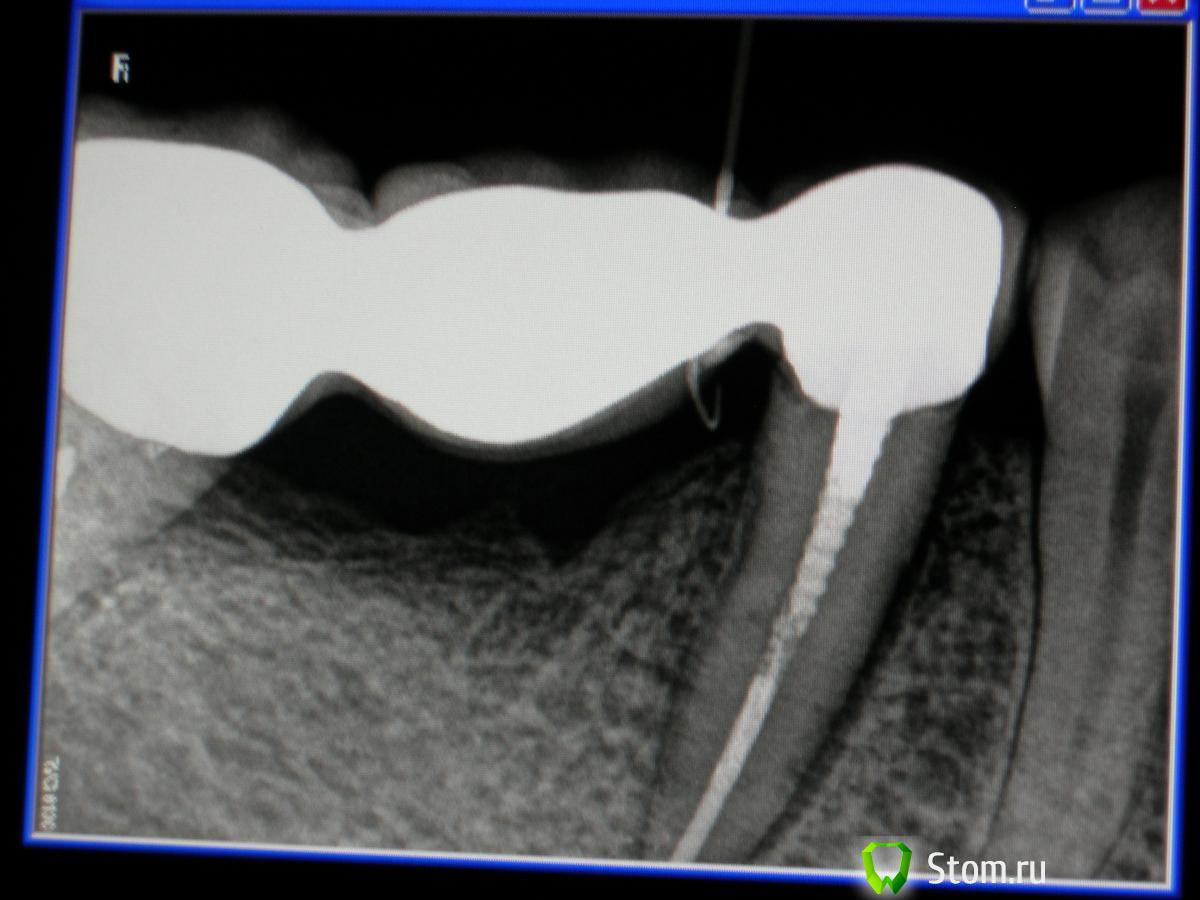

sabi Опубликовано 13 марта, 2012 Поделиться Опубликовано 13 марта, 2012 Дорогие,доктора !Помогите понять в чем причина болей.Начну с начала.В августе 2011 лечила 45 по поводу пульпита.вот контрольный снимок далее этот зуб стал одной из опор мостовидного протеза.Все хорошо,но в декабре появились боли сначала под протезом,а потом и в зубе.Появился свищ,в области межзубного сосочка между 45и46.Вот снимок-в свищ введен гуттаперчевый штифт В итоге мостик сняли,под ним ни пролежней,все чисто.Сейчас зуб беспокоит при накусывании,свищ не уходит,что это может быть?Ортопед настаивает,что я пропустила второй канал.Помогите советом.вот последний снимок Ссылка на комментарий

ннэт Опубликовано 13 марта, 2012 Поделиться Опубликовано 13 марта, 2012 Причина может быть и не в трещине, и не в пропущенном канале, а банально в проталкивании распада за апекс во время инструментальной обработки. Посмотрите периодонтальную щель особенно со стороны 4го. Еще непонятный участок в обл удаленного корня, хотя на остаток не особенно похоже, но если свищ в этой обл. я бы точно сделала кюретаж. А гуттаперча точно в свище? у меня создалось впечатление что она под мостом Ссылка на комментарий

Stomart Опубликовано 13 марта, 2012 Поделиться Опубликовано 13 марта, 2012 Еще непонятный участок в обл удаленного корня, хотя на остаток не особенно похоже, но если свищ в этой обл. я бы точно сделала кюретаж. +1 Остатка нет, но просматривается лунка удаленного корня, проверьте то место. Ссылка на комментарий

stomal Опубликовано 13 марта, 2012 Поделиться Опубликовано 13 марта, 2012 (изменено) Возможно осколки 46, Изменено 13 марта, 2012 пользователем stomal Ссылка на комментарий

sabi Опубликовано 13 марта, 2012 Автор Поделиться Опубликовано 13 марта, 2012 Я тоже думаю на удаленный 46.после того как сняли мост,отдали пациентку хирургу,чтобы сделал там ревизию,а сегодня узнала,что он просто сделал разрез по переходной,а в области свища ничего не смотрел. Ссылка на комментарий